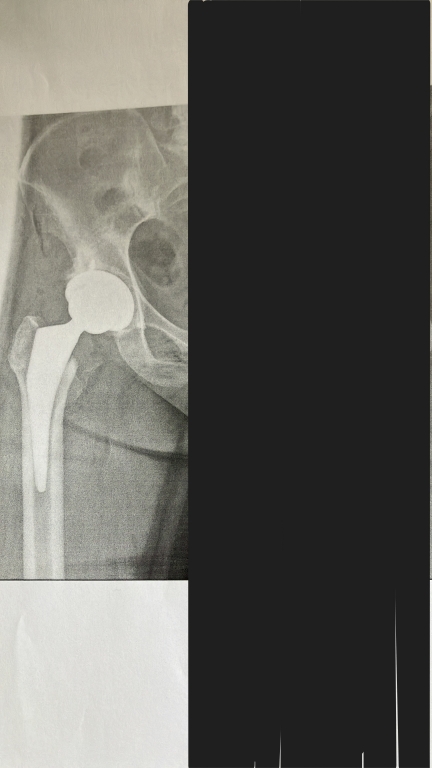

定期巡回・随時対応型訪問介護看護のらうんど千寿の所長です。今回は私が昨年末に股関節置換術のため入院し、いつもは援助する側の私が援助される立場になったことで、いろいろ気づきや学びがあったのでつぶやきます。

また2月に右の股関節置換術が待っていると思うと少し憂鬱ではありますが、病院スタッフの皆さんと再開できることを楽しみに頑張りたいと思います。